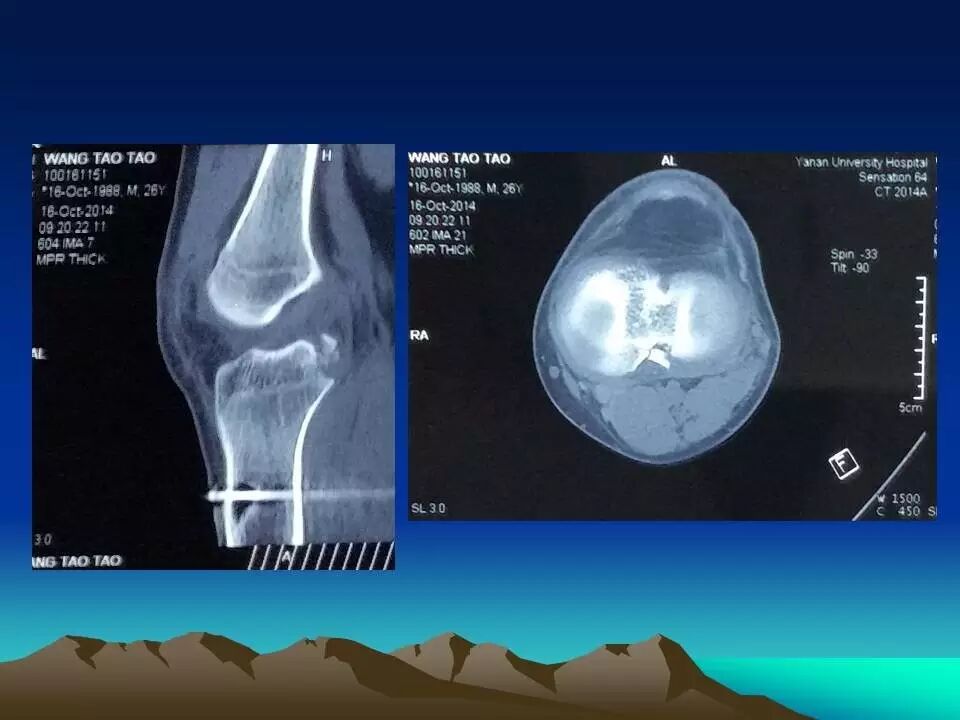

前十字韧带是膝关节重要的前向稳定结构,断裂后可以产生明显的膝关节不稳,严重影响膝关节功能,如果不及时治疗,关节出现反复扭伤,容易引起关节软骨、半月板等重要结构的损害,导致关节过早老化和骨关节病的发生。